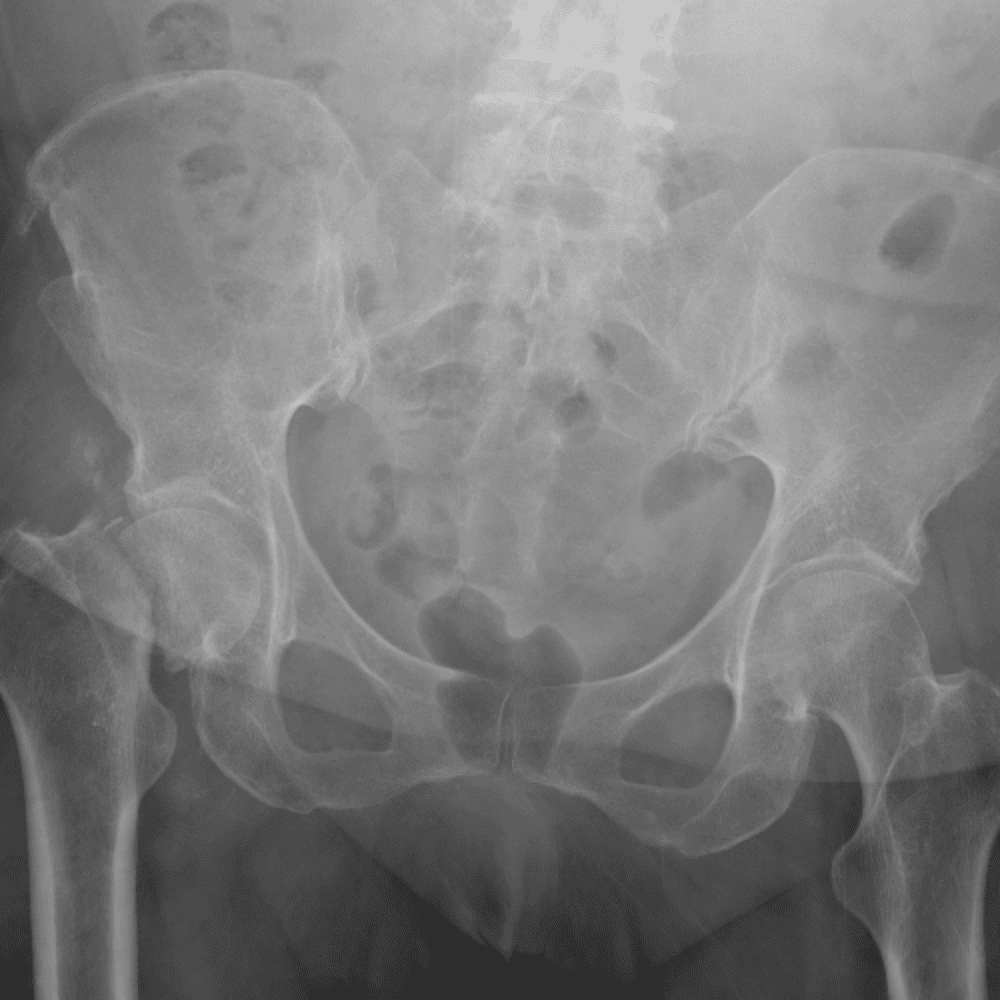

通过包含微妙或困难的病例和一些正常病例来模拟值班。